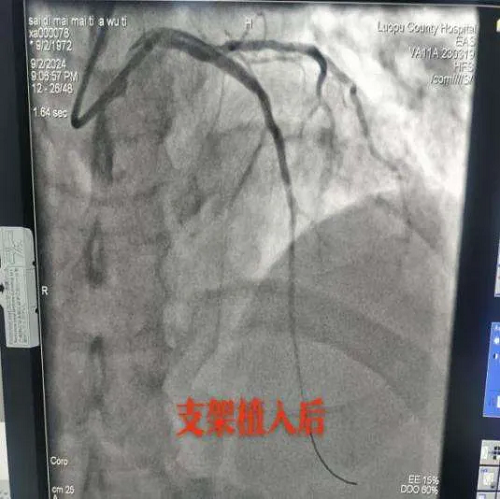

20时15分,冠脉造影提示粗大前降支段完全闭塞,TIMI血流0级,姚远院长及洛浦胸痛中心团队成功为患者开通“罪犯血管”并植入1枚支架,完成血运重建,患者血流恢复正常,患者胸痛胸闷症状明显缓解,生命体征平稳后返回心脏重症监护室。